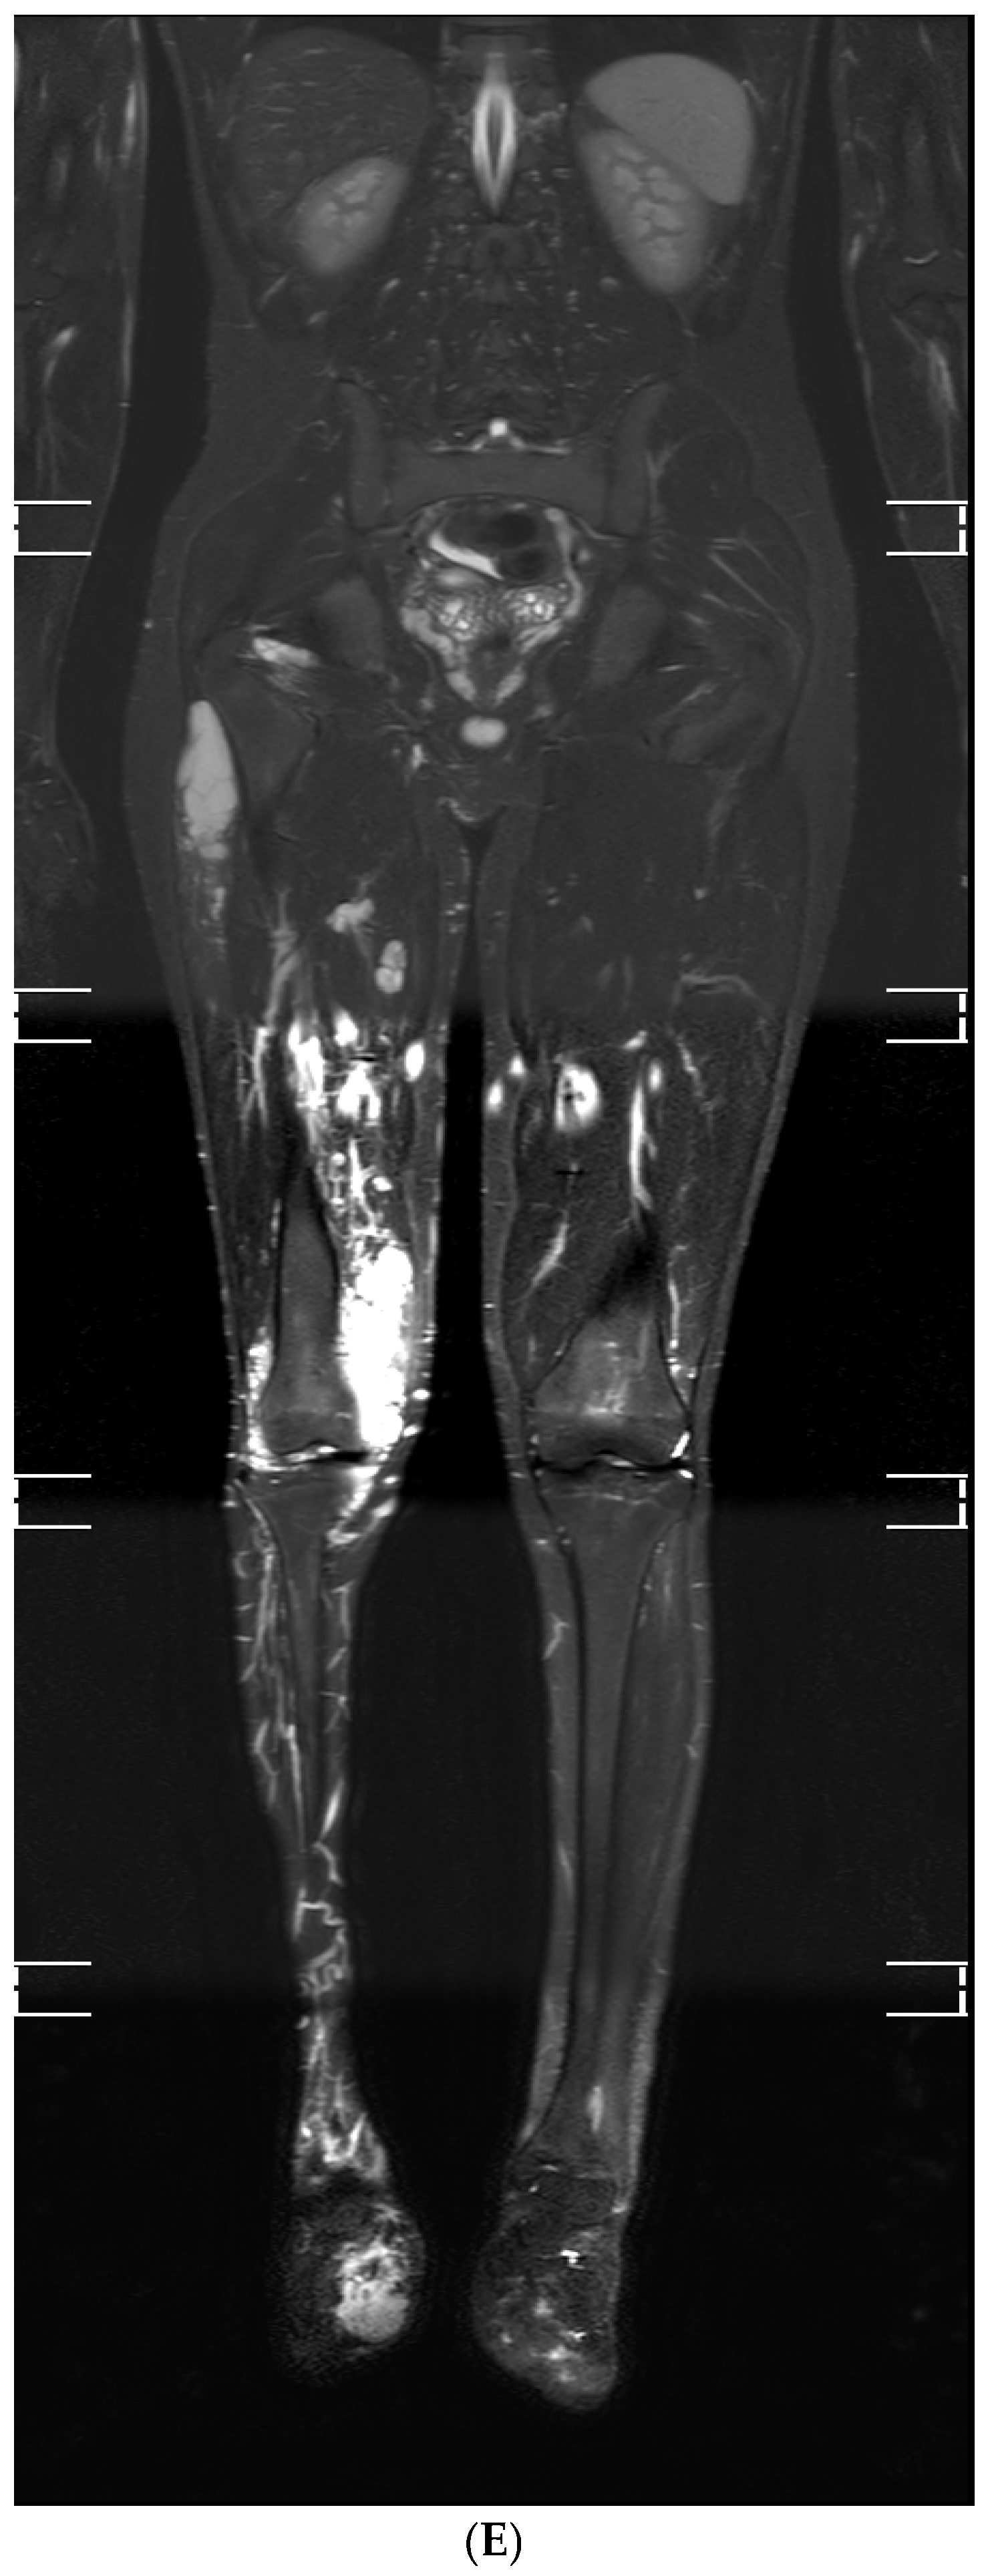

3.3. Radiological Features of VM of the Knee on Contrast-Enhanced MRI

| Patient No. | MRI Sequences Used | Lesion Location | Intra-/Extra-Articular | Extracapsular Structures Involved | Deformation of Affected Limb |

|---|---|---|---|---|---|

| 1 | T1, T2 Fat-Sat, STIR, T2, GRE, T1 Pre-Contrast, T1 Post-Contrast, T1 Post-Contrast Fat-Sat, CE-MRA | Thigh, Hoffa’s fat pad, suprapatellar recess | Both | Subcutaneous tissue, muscles, ligaments | + |

| 2 | T1, T2 Fat-Sat, STIR, PD Fat-Sat, GRE, T1 Pre-Contrast, T1 Post-Contrast Fat-Sat, DWI, CE-MRA | Thigh, crus, Hoffa’s fat pad, suprapatellar recess | Both | Subcutaneous tissue, muscles, ligaments | + |

| 3 | T1, T2, STIR, T2 Fat-Sat, GRE, T1 Pre-Contrast Fat-Sat, T1 Post-Contrast, MRV, CE-MRA | Gluteal region, thigh, Hoffa’s fat pad, suprapatellar recess | Both | Subcutaneous tissue, muscles, ligaments | + |

| 4 | T1, PD, STIR, T2 Fat-Sat, GRE, T1 Pre-Contrast Fat-Sat, T1 Post-Contrast, 3D TOF-MRA, CE-MRA | Thigh, crus, all recesses of knee, Hoffa’s fat pad | Both | Subcutaneous tissue, muscles, ligaments | + |

| 5 | T1, T2, STIR, T2 Fat-Sat, GRE, T1 Pre-Contrast, T1 Post-Contrast, DCE-MRI, CE-MRA | Thigh, Hoffa’s fat pad, suprapatellar recess | Both | Subcutaneous tissue, muscles, ligaments | + |

| 6 | T1, T2, STIR, T2 Fat-Sat, GRE, T1 Pre-Contrast Fat-Sat, T1 Post-Contrast Fat-Sat, MRV, CE-MRA | Gluteal region, thigh, crus, Hoffa’s fat pad, suprapatellar recess | Both | Subcutaneous tissue, muscles, ligaments | + |

| 7 | T1, T2, STIR, T2 Fat-Sat, GRE, T1 Pre-Contrast, T1 Post-Contrast, DTI, CE-MRA | Gluteal region, thigh, crus, foot, Hoffa’s fat pad, suprapatellar recess | Both | Subcutaneous tissue, muscles, ligaments | − |

| 8 | T1, T2, STIR, PD Fat-Sat, GRE, T1 Pre-Contrast, T1 Post-Contrast Fat-Sat, DWI, CE-MRA | Crus, Hoffa’s fat pad, suprapatellar recess | Both | Subcutaneous tissue, muscles, ligaments | + |

| 9 | T1, T2, STIR, T2 Fat-Sat, GRE, T1 Pre-Contrast Fat-Sat, T1 Post-Contrast Fat-Sat, 3D TOF-MRA, CE-MRA | Hoffa’s fat pad, suprapatellar recess | Intra-articular | − | − |